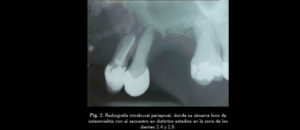

228 – Impacto de la CBCT en la toma de decisión del tratamiento relacionado a extracción de terceros molares impactados.

El objetivo del presente estudio fue evaluar los factores (referidos a la CBCT) que influyen en la toma de decisión en tratamientos para extracción de